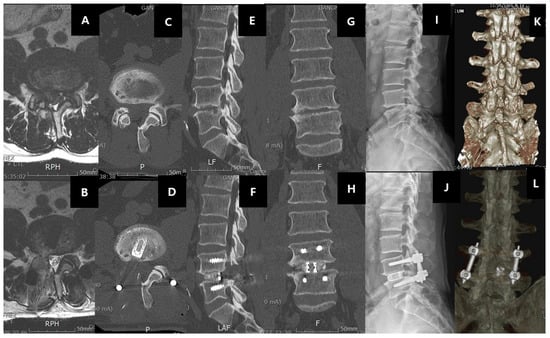

11.3.2. Degenerative Disc Disease with or without Spinal Stenosis

11.4. Recent Development of Endoscopic Spine Surgery and Its Role in Degenerative Disc Diseases